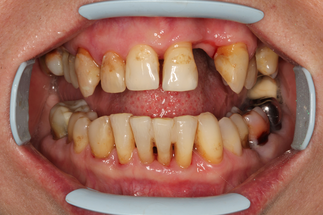

В основной группе 3 проводили фотодинамическую терапию с помощью препарата «Гелеофор» и светодиодного аппарата АФС «Спектр». По сравнению с традиционной антимикробной терапией с применением геля «Метрогил-Дента», противовоспалительный эффект которой наблюдался лишь после завершения всего курса лечения, пациенты группы 3 почувствовали улучшение своего состояния непосредственно на стоматологическом приеме после проведения фотодинамической терапии. После первого сеанса 24,0% пациентов отмечали снижение дискомфорта и болевых ощущений в полости рта, на которые жаловались до лечения. После второго сеанса ФДТ уже 62,0% пациентов субъективное улучшение. После третьего сеанса практически все пациенты (92,0%) отмечали улучшение состояния пародонта, снижение кровоточивости при чистке зубов, уменьшение воспаления десны и болевых ощущений. Улучшение состояния тканей пародонта подтверждалось и при объективном обследовании полости рта (Рисунок 14).

| Клиническая картина до лечения | Ортопантомограмма до лечения |

| Проведена профессиональная гигиена | Обработка ПК гелем «Гелеофор» |

| Активация фотосенсибилизатора | Состояние после первого сеанса ФДТ |

| Состояние после второго сеанса ФДТ | Состояние после третьего сеанса ФДТ |

| Рисунок 14. Динамика состояния тканей пародонта у пациента с ХГП тяжелой степени группы 3 в ходе проведения курса фотодинамической терапии. | |